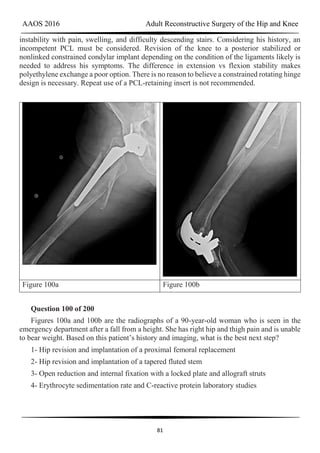

Figure 56a Figure 56b Figure 56c

Question 56 of 200

Figures 56a through 56c are the radiographs of a 65-year-old man with a 6-week history

of severe left hip pain. He had a left total hip arthroplasty 19 years ago and a femoral revision

10 years ago. His erythrocyte sedimentation rate (ESR) and C-reactive protein (CRP) level are

within defined limits. What is the most appropriate next step?

1- A trial of limited weight-bearing activity and physical therapy

2- A triple-phase bone scan to evaluate for loosening

3- Acetabular component revision

4- Femoral component revision

PREFERRED RESPONSE: 4- Femoral component revision

DISCUSSION

AAOS 2016 Adult Reconstructive Surgery of the Hip and Knee

45

The radiographs reveal a fracture of the extensively porous coated stem. This entity,

although rare, is associated with higher risk for occurrence when thin stems are implanted in

patients with thick cortices and there is a lack of proximal stable support for the prosthesis.

Nonsurgical care likely would not help this patient. A triple-phase bone scan would not add

any information that would change the treatment plan.